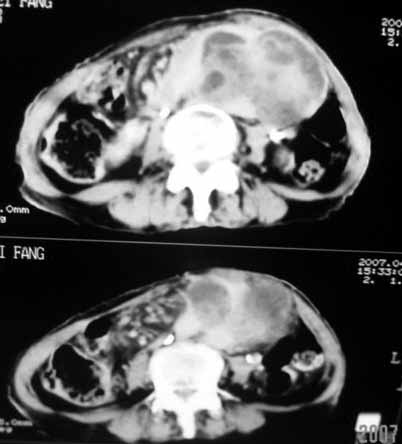

以下是引用天南地北在2007-4-30 17:42:00的发言:[br]增强扫描显示腹主动脉给包绕、推移。肿块不规则强化,[br]修正我在平扫的诊断[br]支持考虑:间叶源性肿瘤可能性大

以下是引用余辉在2007-4-30 18:01:00的发言:[br]病灶前方的条状增强影是什么?若是胰腺,位置似乎有点低,若是十二指肠,似乎又不诫该是那样强化,姑且将其看作胰腺吧,那么考虑来源于胰腺粘液囊腺瘤可能性大,其次考虑来源于肠系膜或者后腹膜的肿瘤如平滑肌肉瘤,异位嗜铬细胞瘤及淋巴瘤等。

以下是引用zyx168在2007-4-30 23:24:00的发言:[br]考虑:间叶源性肿瘤可能性大